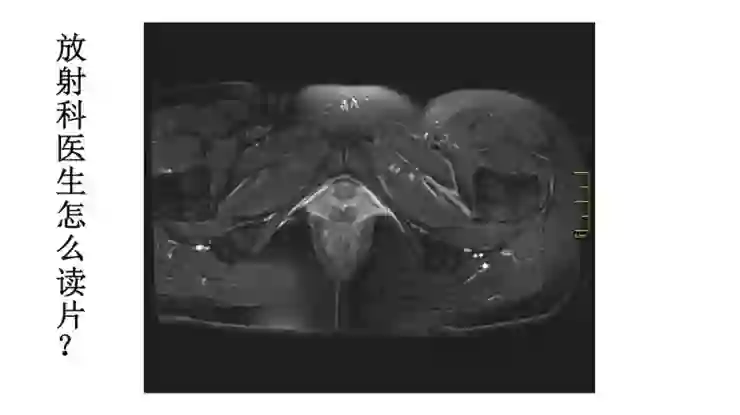

所以放射科医生是怎么读片?就是一层一层地观察图像。举个例子,这是一个T2加权像序列,可以看到膀胱,尿液是亮的,然后能看到子宫,然后能看到双侧卵巢,接着是宫颈,宫颈再往下一层一层延续下去就是阴道。

放射科大夫首先要了解正常的结构,先知道正常是什么样,然后出现一个异常改变的时候就会很敏感的发现病灶所在。